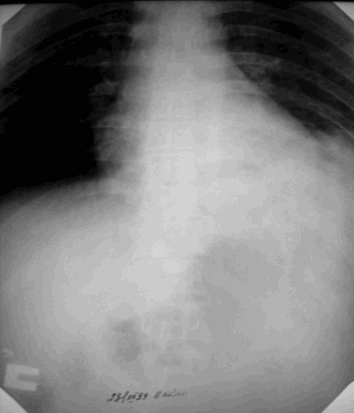

Травма грудной клетки, переломы ребер, переломы грудины, пневмоторакс,гемоторакс,

эмфизема мягких тканей